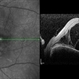

- OCT of 29-year-old female with serous detachment OS.